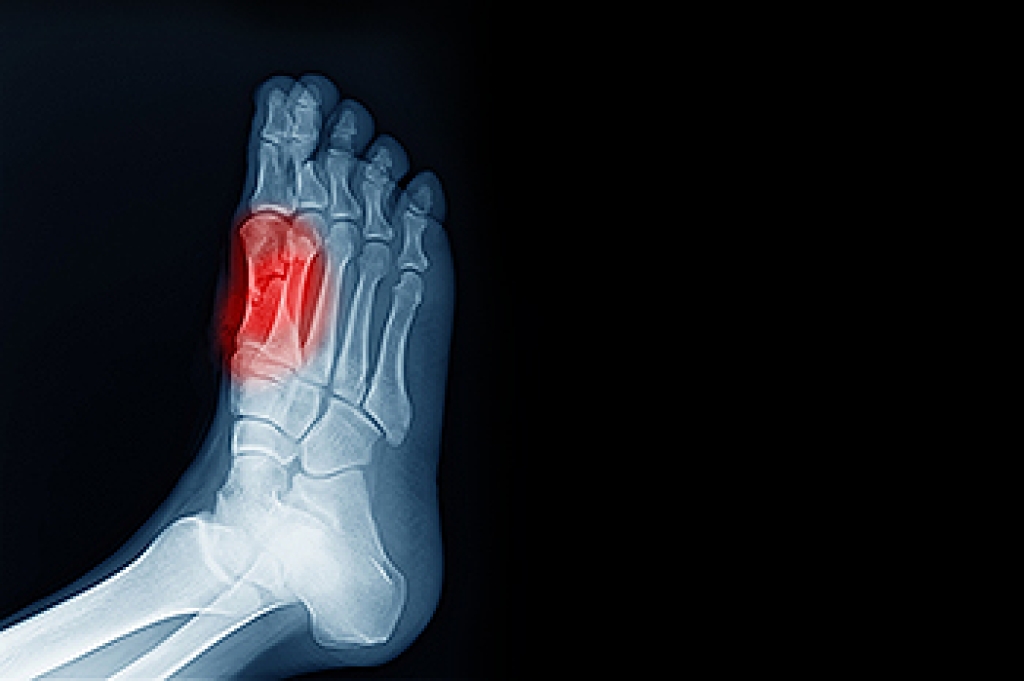

Someone would seek the care of a podiatrist if they have suffered a foot injury or have common foot ailments such as heal spurs, bunions, arch problems, deformities, ingrown toenails, corns, foot and ankle problems, etc.

A podiatrist will treat the problematic areas of the feet, ankle or lower leg by prescribing the following:

- Surgery on lower extremity fractures